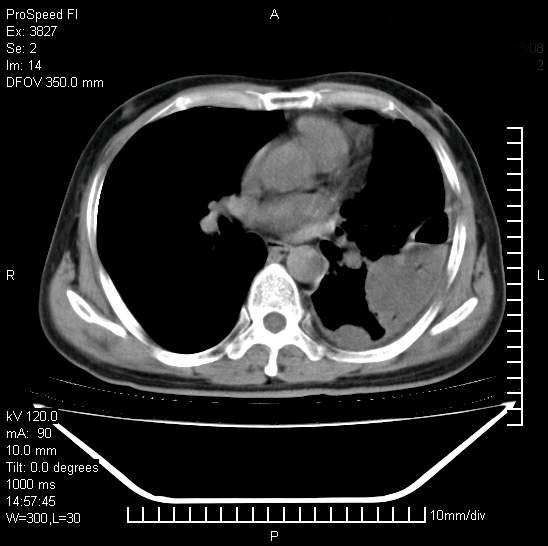

男性,一月前出现右侧肋区疼痛,较剧烈,干咳,无发热,自诉使用抗炎药后缓解,几天前又出现左侧剧烈疼痛,

发热,体温38。9,今天ct,考虑左侧包裹性脓胸,胸腔积液,右上中肺小斑片影,结核/炎症?胸水未见恶性细胞。